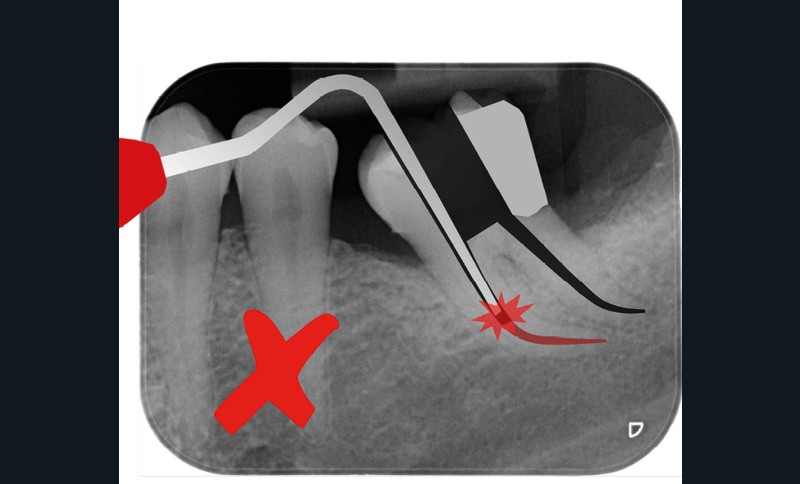

Trop petite

Une cavité d’accès trop petite [2] optimiserait le pronostic biomécanique (préservation dentaire maximale) mais pourrait compromettre le pronostic endodontique : mauvaise lecture de l’anatomie, instrumentation partielle, non ergonomique et avec risque de fracture, défaut de nettoyage des parois canalaires [3], irrigation inadéquate, difficulté d’obturation canalaire, voire d’obturation coronaire. Ce sera le cas des cavités d’accès « Ninja » [4] ou ultraconservatrice (fig. 1), des cavités d’accès « Truss » [5] (fig. 2), des cavités d’accès dites « opportunistes » [6] (fig. 3).